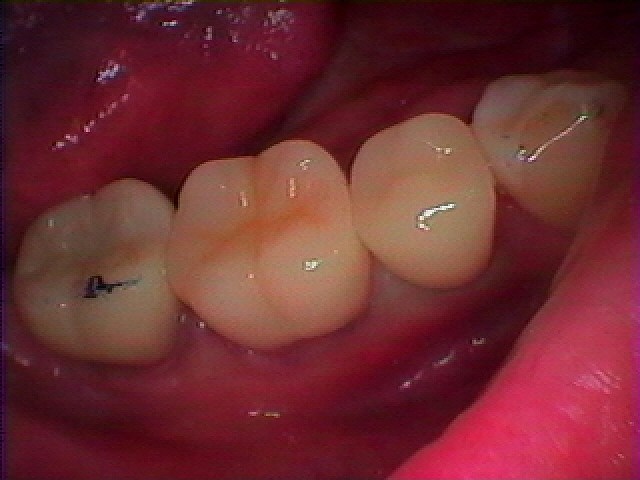

右下5,6番の銀歯をはずして白いセラミックにやり変えてきれいにしたい|お知らせ |広島市安佐南区の歯科医院 右下5,6番の銀歯をはずして白いセラミックにやり変えてきれいにしたい トップ お知らせ・ブログ お知らせ 右下5,6番の銀歯をはずして白いセラミックにやり変えてきれいにしたい 右下5,6番の銀歯をはずして白いセラミックにやり変えてきれいにしたい この銀歯2つをきれいにしたいとのこと 6番の被せを外していきました 中の土台もすぐに取れてきました 根幹治療から行っていきます ファイバーコアにて支台築造を行っています このように本来の歯のようにきれいに仕上がりました セレックセラミックにて修復しています しぜんな白さになりました Web診療予約 初めての方へ 選ばれ続ける理由 院内設備について 歯が痛いしみる一般歯科 歯がぐらぐらする歯周病 健康な歯を保ちたい予防歯科 子供の虫歯予防をしたい小児歯科 銀歯をセラミックに審美歯科 白い歯を目指しませんか?ホワイトニング 矯正専門医がいるので安心矯正歯科 抜けた歯を補いたいインプラント・入れ歯 医院案内 スタッフ紹介 メリィハウス歯科クリニックオフィシャルホームページ ラベンダー歯科クリニックオフィシャルホームページ お知らせ・ブログ ホーム 診療科目 一般歯科 歯周病治療 予防治療 小児歯科 審美治療 ホワイトニング 矯正歯科 入れ歯・インプラント マウスピース矯正 初めての方へ 院長・スタッフ 設備紹介 医院案内・アクセス メニューを閉じる